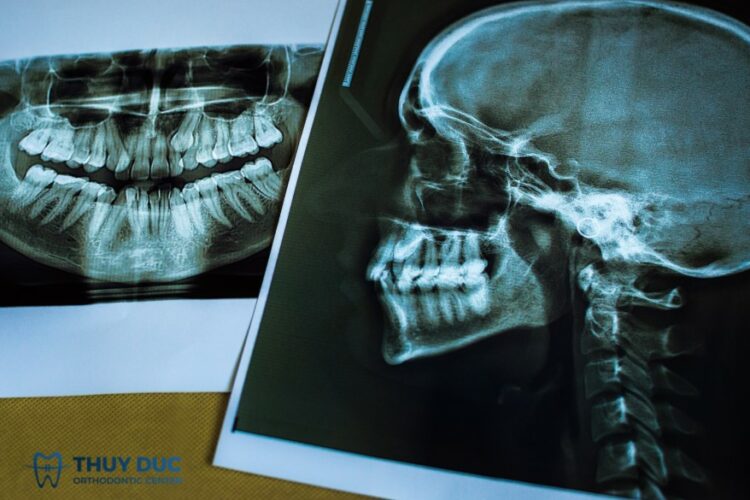

Để lên được kế hoạch điều trị, bác sĩ sẽ không chỉ nhìn vào tình trạng răng mọc như thế nào, mà còn cần phân tích tổng thể toàn bộ hệ thống:

- Chụp phim X-quang (Cephalometric & Panoramic) để đánh giá cấu trúc xương hàm và vị trí chân răng.

- Scan hàm 3D để đo lường chính xác độ lệch khớp cắn, overbite, overjet, tương quan răng cối, răng nanh…